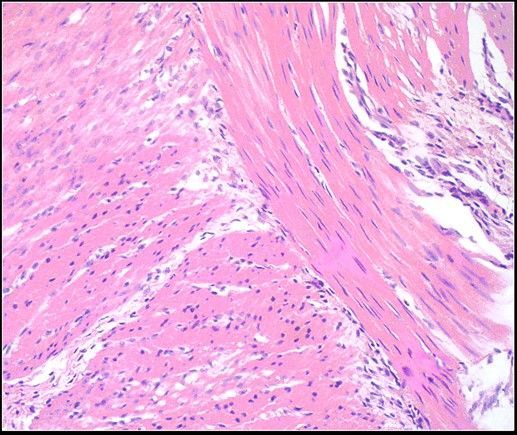

Question 2

Question

Label this Image First Dot: Name Second Dot: Staining

Image:

7977fb9c-8c0c-4441-968d-860ac5f40473 (image/jpeg)

Answer

Smooth Muscle Tissue

HE